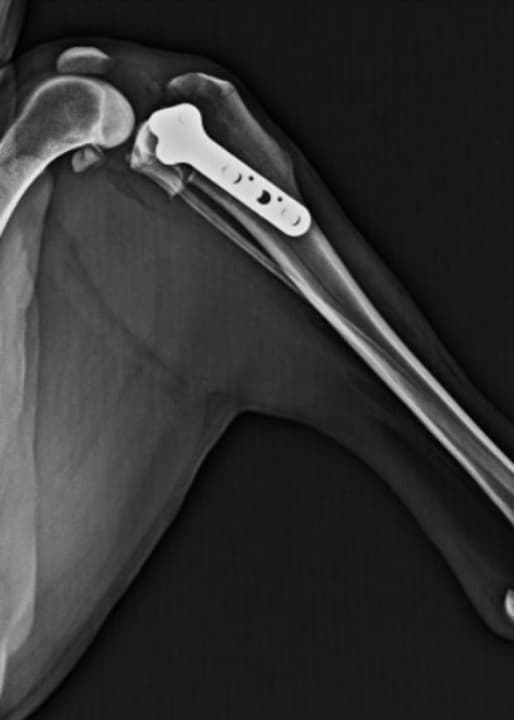

脛骨高平部水平化骨切り術(TPLO)は、脛骨を切ってプレートで固定することにより、脛骨の頭側への移動を防ぎ、膝を安定化させる手術です。

8kgを超えるワンちゃんには、この術式で行うことが多いです。